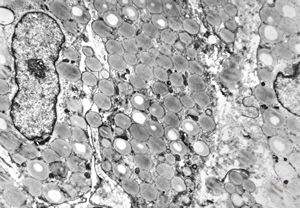

celiakia … reduced microvilli, lipid droplets